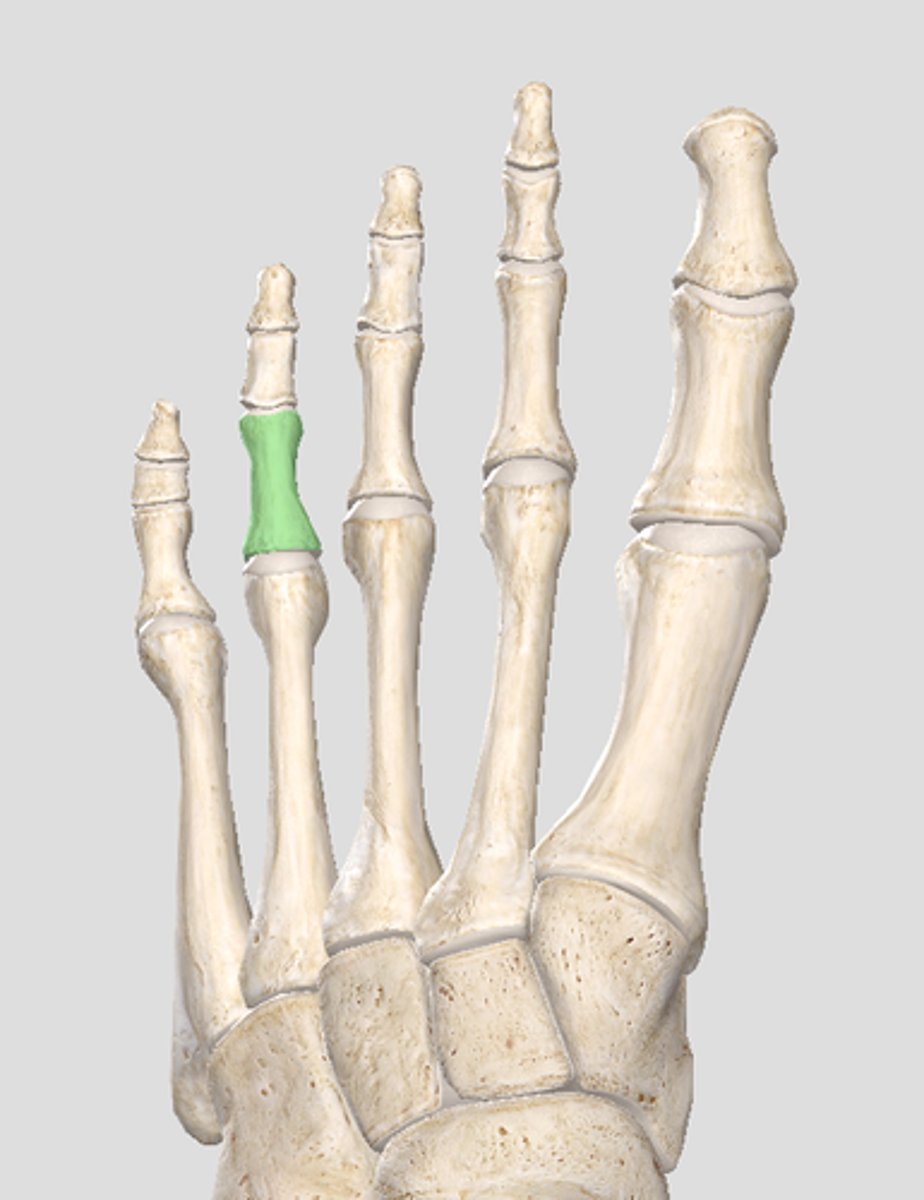

Proximal phalanx of digit 2

Middle phalanx of digit 2

Distal phalanx of digit 2